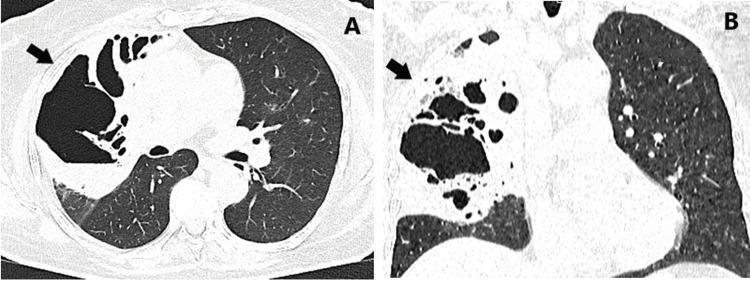

巨大坏疽性肺脓肿一例罕见病例。

A Rare Case of Giant Gangrenous Lung Abscess.

Gangrenous lung abscess (LA) is a limited form of lung gangrene. Although its frequency has decreased dramatically in recent years, it occupies an important place in clinical practice. Delaying its diagnosis or incorrect treatment leads to a risk to the patient's life. Timely diagnostics and treatment reduce morbidity and mortality rates. А 68-year-old woman who underwent a right upper bilobectomy for a gangrenous LA is presented. The case is considered in the context of the prolonged therapeutic course and the need for surgical treatment.

摘要

坏疽性肺脓肿(LA)是肺坏疽的一种局限形式。尽管近年来其发病率已大幅下降,但在临床实践中仍占有重要地位。延误诊断或治疗不当会危及患者生命。及时诊断和治疗可降低发病率和死亡率。本文介绍了一名68岁因坏疽性肺脓肿接受右上叶双肺叶切除术的女性患者。结合其漫长的治疗过程和手术治疗的必要性对该病例进行了分析。